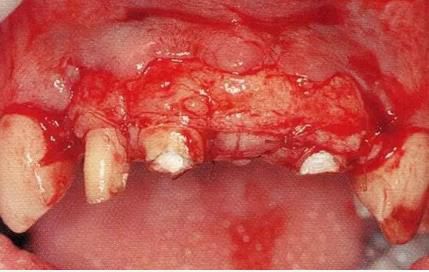

圖15-5  橋體部增大的同時通過APF將鄰接牙牙周袋去除。同時進行上唇系帶的切除。

圖15-6  治愈期間對臨時修復體進行形態(tài)修整。